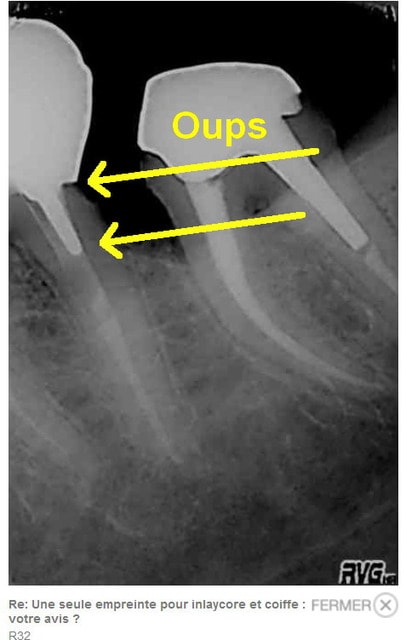

"dit chicot 29 , c'est alesé avec des instruments de quelle taille ces canaux?"

Sx protaper, largo numero 3, re sx pour se rapprocher de l'apex puis s1, s2, f1 f2 protapers. Depuis 4 mois j'ai remplacé s2, f1 f2 par r25 réciproc voir r40.

Ce matin finition r40, pas d'empreinte pour ic, je ne disposais que d'une demi-heure et devis non établi.

Fuck j'arrive pas à virer la radio avec l'inlay core.

1. c'est une 6, 2. c'est pas une de mes réalisations et ça a au moins 12 ans, comme quoi !